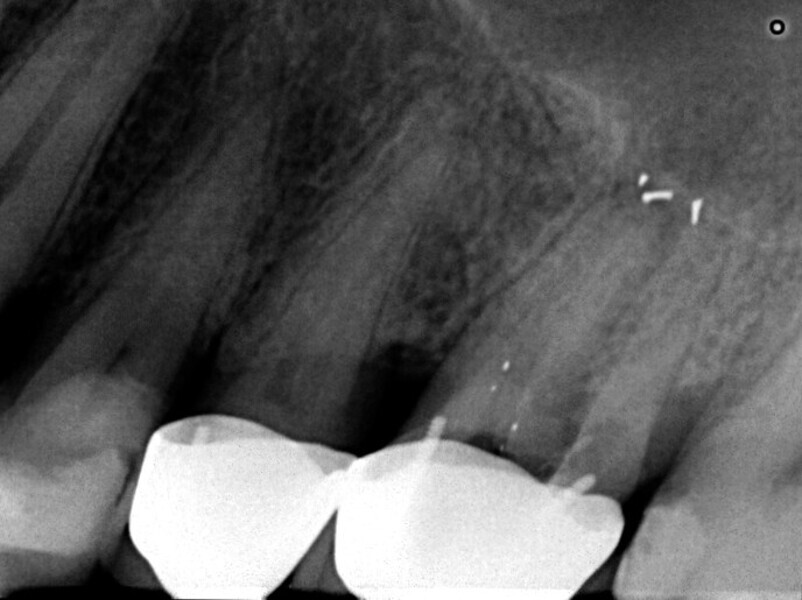

Maxillary sinus and root canal therapy complications